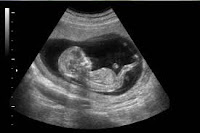

Sin embargo, ello es exactamente lo que ocurre en los cada vez más numerosos embarazos que se logran por medio de la fecundación in vitro (FIV). El diario The New York Times publicó un artículo que describía la creciente tendencia en las mujeres que utilizan esta técnica y que “reducen” sus embarazos múltiples a un solo feto. Guiado por un ultrasonido, el médico inserta una aguja directamente en el pecho del bebé por nacer que no es deseado y le inyecta cloruro de potasio, el mismo fármaco que se utiliza en la ejecución por inyección letal de aquellos que han sido condenados a la pena de muerte. La inyección causa un paro cardíaco y el bebé por nacer muere. El sistema inmunológico de la madre desintegra el cadáver de la criatura y el organismo de la gestante lo reabsorbe. ¿Qué impulsa a una madre a dar su consentimiento a semejante barbarie?